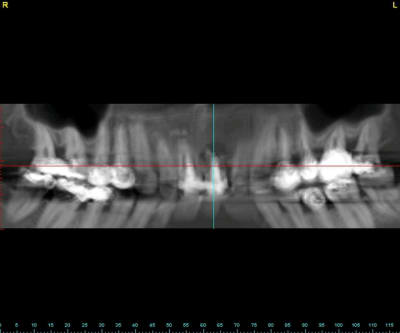

un autre cas EII MCI sur 11/21...mais en photos (j'ai aussi la vidéo, faut que je la passe sur youtube)